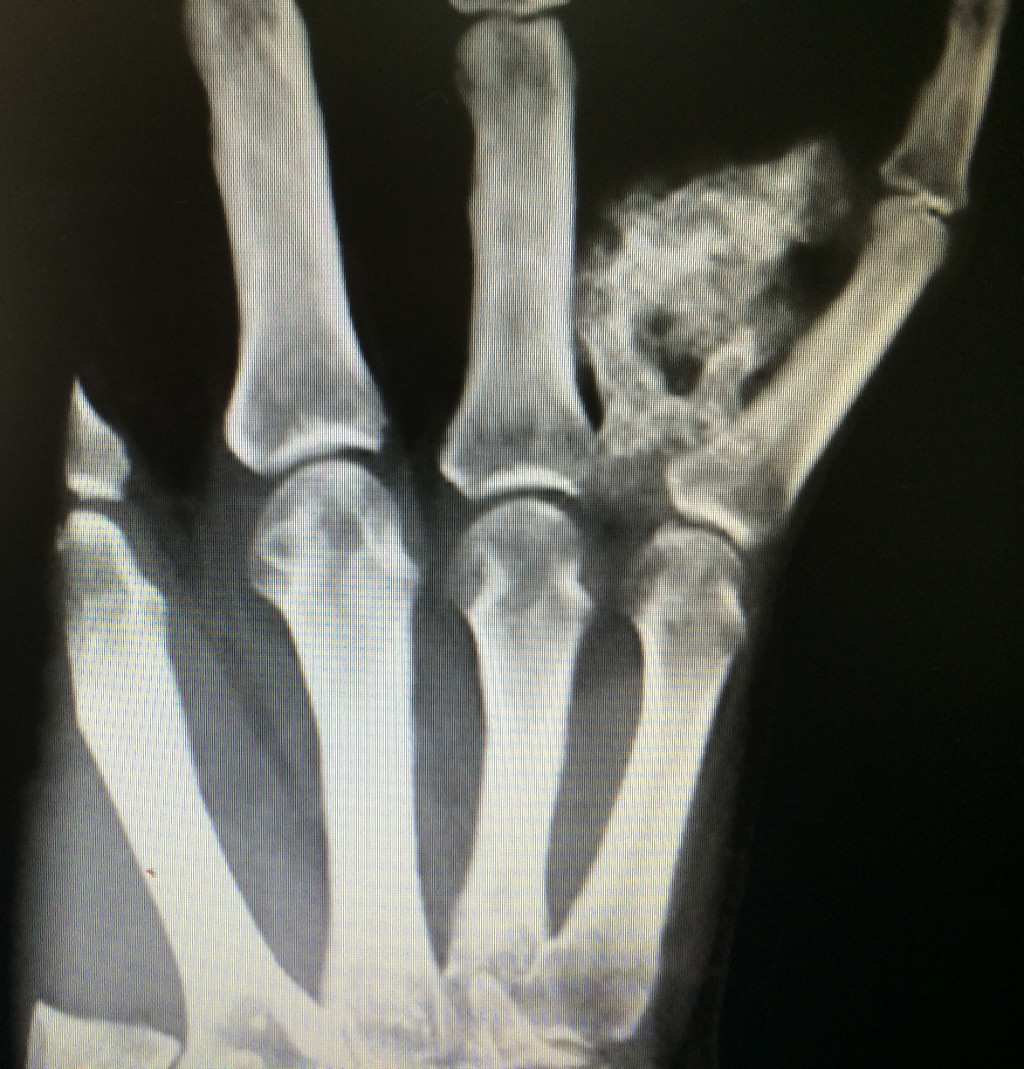

- Case 1